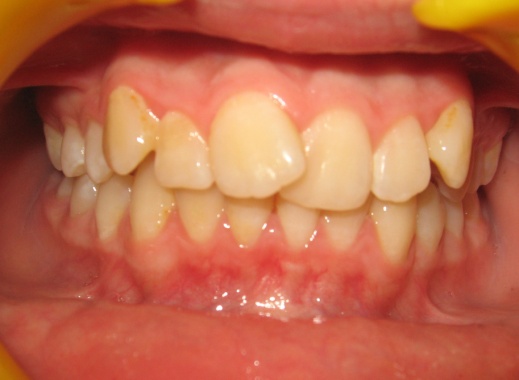

1 - Arcades dentaires avant-après

Les photos montrent un encombrement dentaire important associé à une classe II dentaire. Les extractions de prémolaires ont été décidées non seulement pour créer la place nécessaire à l’alignement, mais aussi pour corriger le décalage de classe II. Le résultat final illustre qu’un plan de traitement bien réfléchi peut répondre simultanément aux impératifs fonctionnels et esthétiques, sans compromettre l’harmonie faciale.

Le recul progressif des dents encombrées dans les espaces d’extraction créés à cet effet a été rendu possible grâce à l’utilisation de brackets autoligaturants, particulièrement efficaces pour respecter l’angulation et le torque des dents. Tous les espaces d’extraction ont été exploités pour résoudre l’encombrement, évitant ainsi tout recul des dents antérieures. L’occlusion obtenue est physiologique, en classe I canine et en classe II molaire thérapeutique.